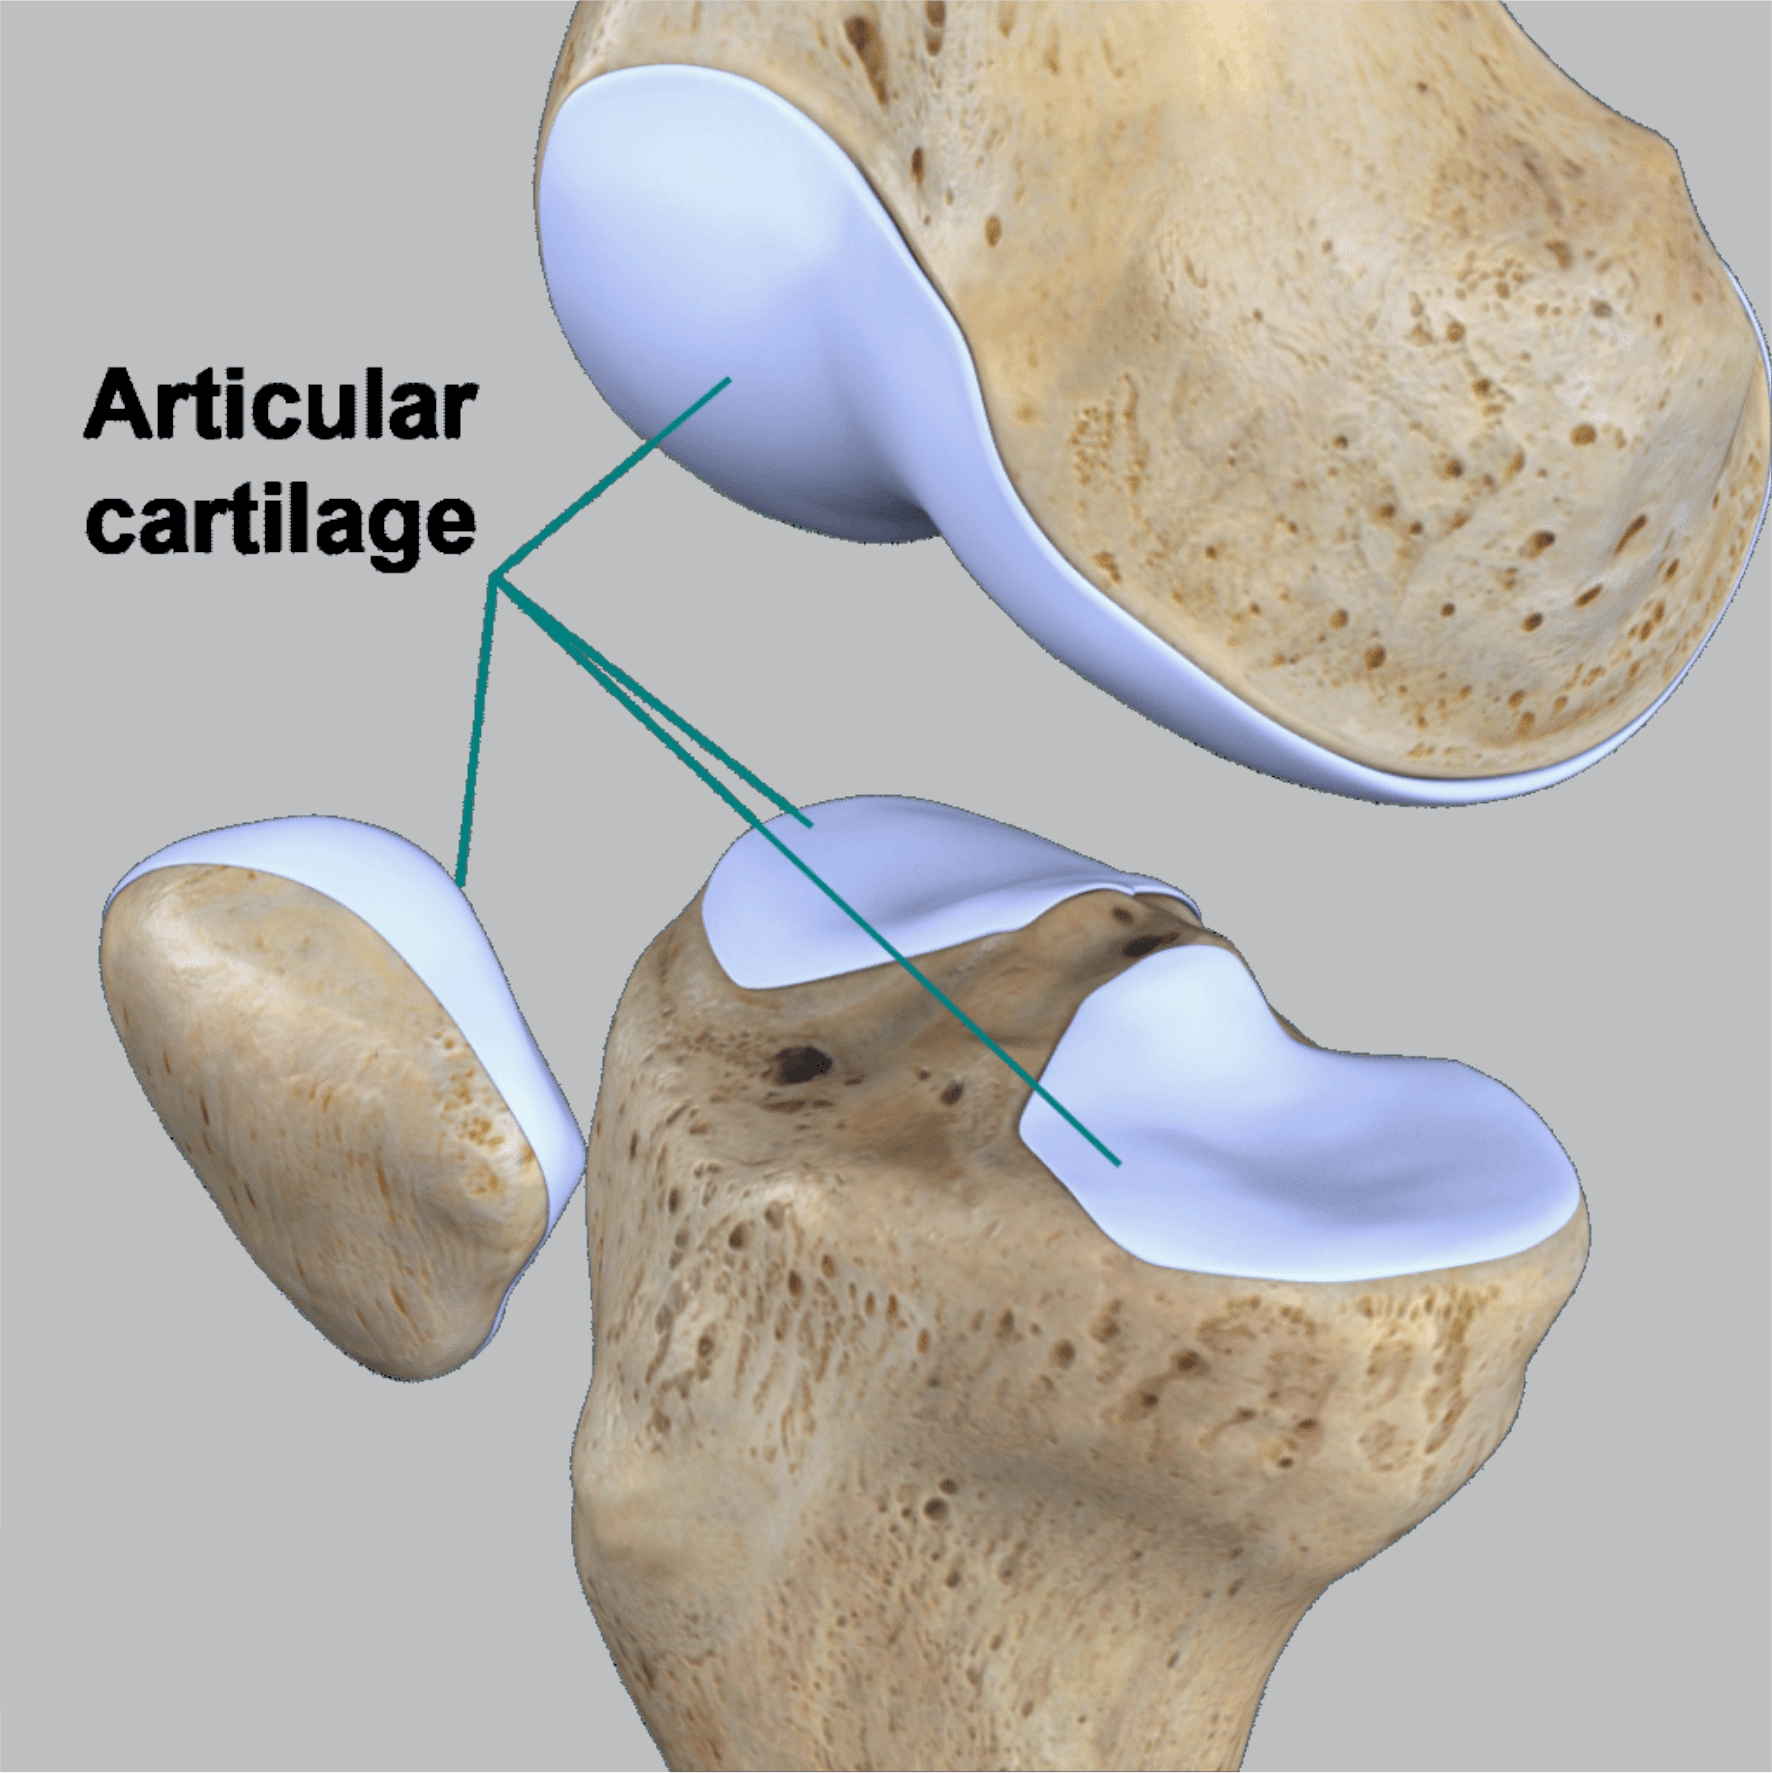

آیا PRP غضروف های آسیب دیده را بازسازی می کند؟؟؟